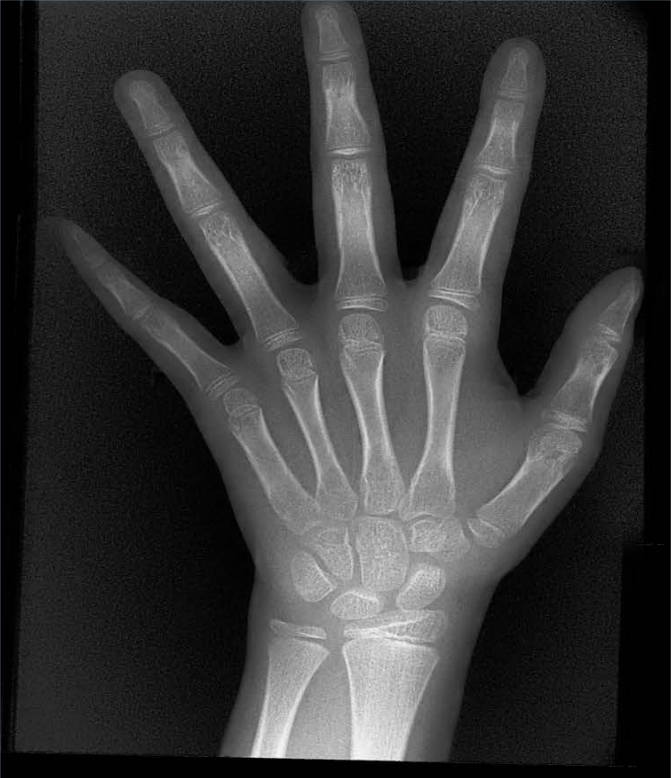

X射線骨齡儀通過拍攝兒童手腕部(指骨、掌骨、腕骨)的X射線影像,依據(jù)骨骼的形態(tài)、大小、鈣化程度等特征,結(jié)合評估標(biāo)準(zhǔn)(如《中國青少年兒童手腕骨成熟度及評價方法》,簡稱《中華-05》標(biāo)準(zhǔn))進(jìn)行骨齡判定。相較于傳統(tǒng)檢測方式,X射線骨齡儀具有輻射劑量低、影像清晰度高、檢測效率高的優(yōu)勢,能精準(zhǔn)捕捉骨骼發(fā)育的細(xì)微變化,為骨齡評估的準(zhǔn)確性提供保障。